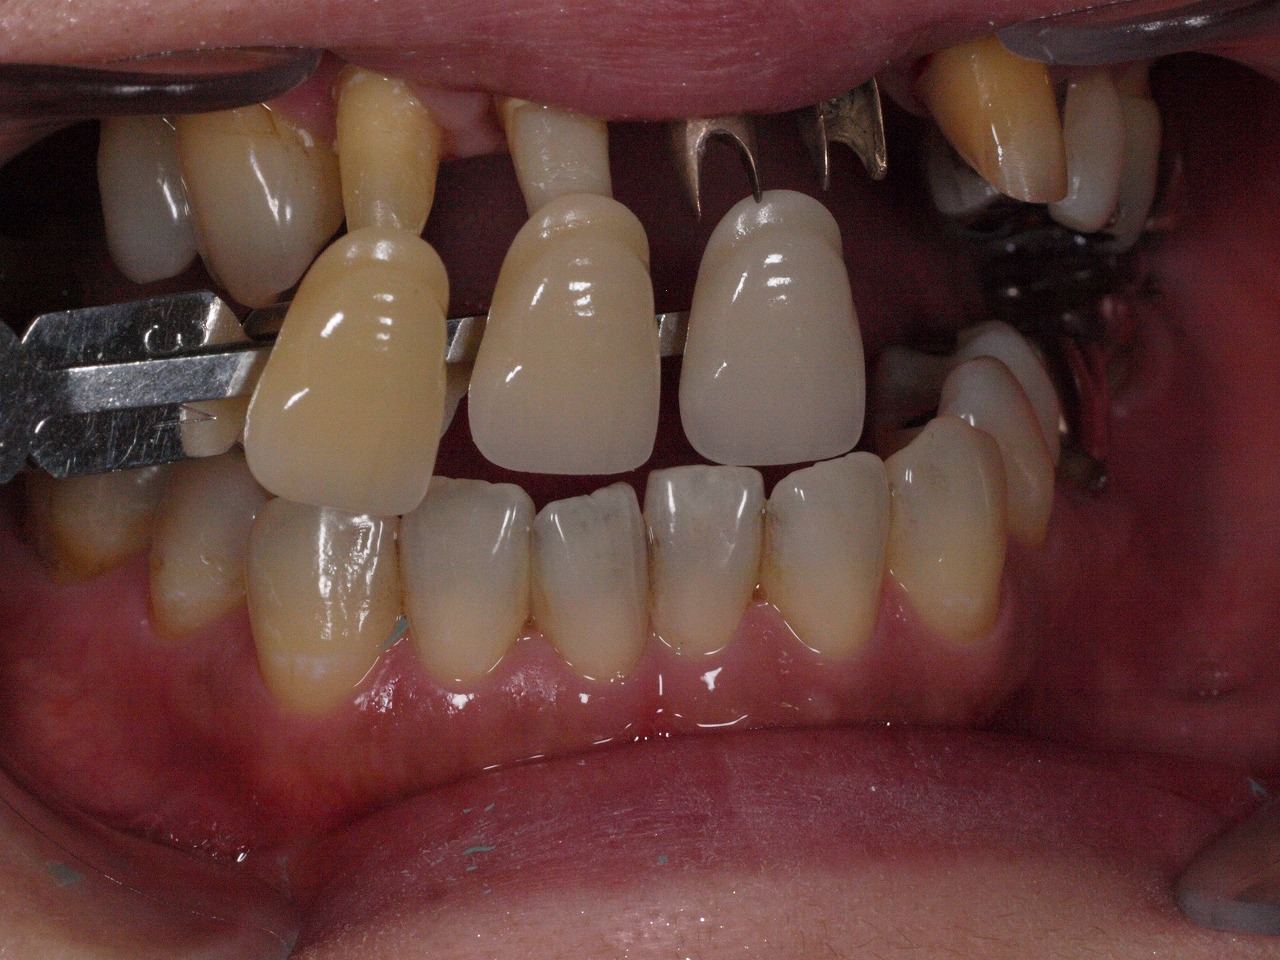

前歯部のインプラント治療 重度の歯周病が進んだ結果のインプラント治療|お知らせ |広島市安佐南区の歯科医院 前歯部のインプラント治療 重度の歯周病が進んだ結果のインプラント治療 トップ お知らせ・ブログ お知らせ 前歯部のインプラント治療 重度の歯周病が進んだ結果のインプラント治療 前歯部のインプラント治療 重度の歯周病が進んだ結果のインプラント治療 術前になります 前歯部も動揺にてフレアーアウトしています 前歯部は動揺歯のため抜歯と固定のために仮歯にしています 抜歯後4か月になります インプラント埋入時になります シェード合わせを行っています 術前術後のパノラマになります 動揺歯の固定のためクラウンへ置き換えています Web診療予約 初めての方へ 選ばれ続ける理由 院内設備について 歯が痛いしみる一般歯科 歯がぐらぐらする歯周病 健康な歯を保ちたい予防歯科 子供の虫歯予防をしたい小児歯科 銀歯をセラミックに審美歯科 白い歯を目指しませんか?ホワイトニング 矯正専門医がいるので安心矯正歯科 抜けた歯を補いたいインプラント・入れ歯 医院案内 スタッフ紹介 メリィハウス歯科クリニックオフィシャルホームページ ラベンダー歯科クリニックオフィシャルホームページ お知らせ・ブログ ホーム 診療科目 一般歯科 歯周病治療 予防治療 小児歯科 審美治療 ホワイトニング 矯正歯科 入れ歯・インプラント マウスピース矯正 初めての方へ 院長・スタッフ 設備紹介 医院案内・アクセス メニューを閉じる